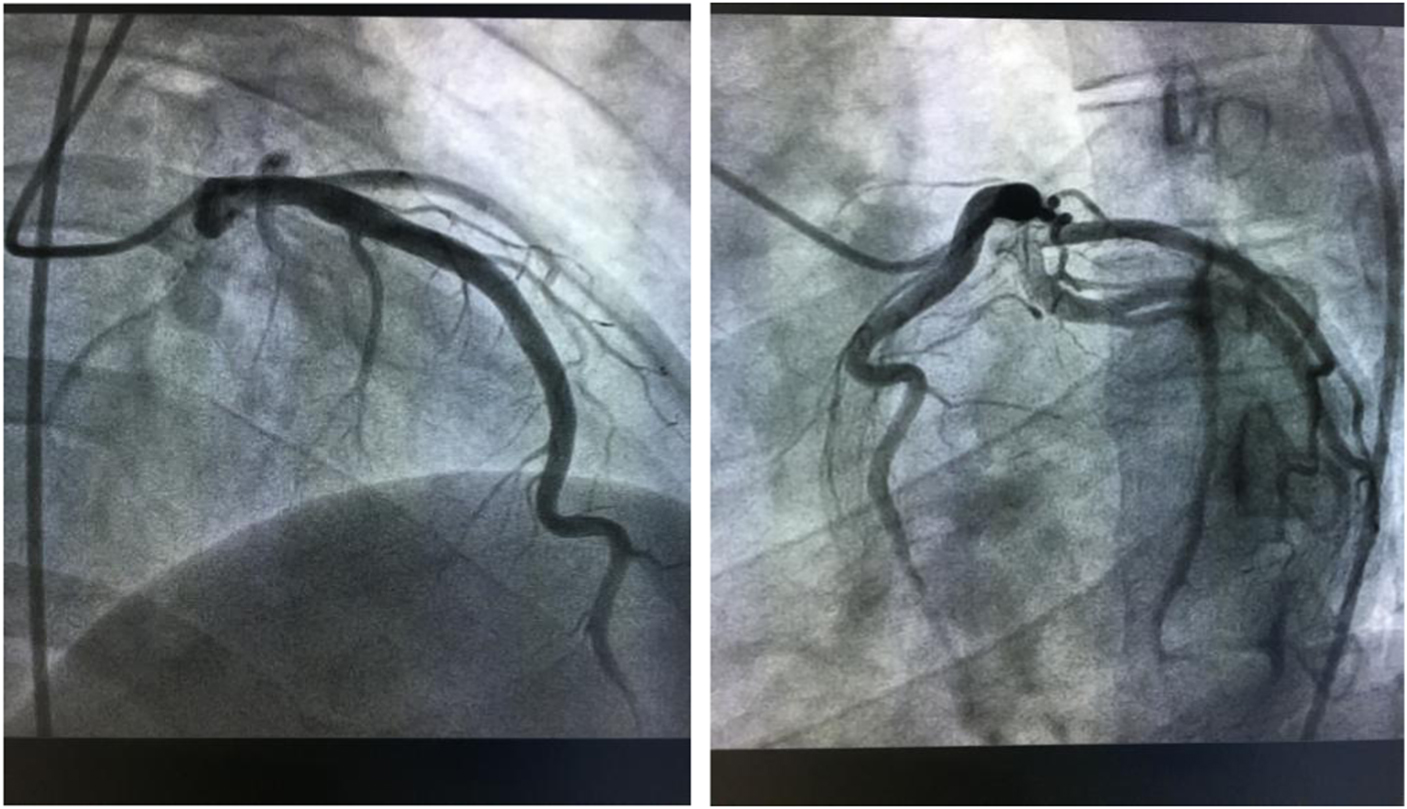

According to the results, our preliminary diagnosis was acute inferior myocardial infarction (Killip grade I) combined with nephrotic syndrome, and we performed a percutaneous intervention procedure, which was followed by 300 mg aspirin and 300 mg clopidogrel orally immediately. During the operation, we saw that the left coronary artery had thickened and the left main artery, left circumflex artery, and right coronary artery were normal. However, there was a great deal of thrombi blocking the anterior and middle anterior descending branch, resulting in 95% stricture (Fig 2) and leading to bloodstream classification at thrombolysis and thrombin inhibition in myocardial infarction grade II. Next, we applied the thrombus suction technique and injected 13 ml of tirofiban to dissolve blood clots. Unfortunately, there was still medium thrombi remaining and 60% stricture in the re-examination of coronary arteriography (Fig 3). The bloodstream classification at thrombolysis and thrombin inhibition in myocardial infarction grade III. Because the anterior descending branch dilatation made it unsuitable for stent implantation, we had to stop further operation. Next, we gave him a therapeutic regimen of low-molecular-weight heparin for 7 days, 100 mg aspirin per day, and 90 mg ticagrelor twice a day to fight platelet aggregation, and 40 mg atorvastatin per night to remedy hyperlipidaemia persistently.

Figure 3 After the thrombus suction operation.

One day after the operation, his postoperative electrocardiogram showed that the elevated ST segments in II, III, aVF, and V4–V6 were down to baseline, and an inverted T wave began to appear in V2–V6 (Fig 4). An echocardiography performed 3 days after admission showed a left ventricular ejection fraction of 48.2%, enlarged bilateral atrium, dilated left ventricle, segmental weak pulse of left ventricular wall, mild regurgitation of bicuspid valve or of tricuspid valve, and the estranged left ventricular cells (Figs 5–7). Laboratory tests on the same day showed a higher troponin I of 31.833 ug/L, lower myoglobin of 27.9 ug/L, creatine kinase-MB of 21 U/L, creatine kinase of 74 U/L, and lactate dehydrogenase of 489 U/L. After 4 days, the serum laboratory results showed the following results: troponin I, 6.912 ug/L; myoglobin, 29.5 ug/L; creatine kinase-MB, 17 U/L; creatine kinase, 36 U/L; lactate dehydrogenase, 330 U/L; cholesterol, 2.86 mmol/L; low-density lipoprotein cholesterol, 1.63 mmol/L; triglyceride, 2.28 mmol/L; and high-density lipoprotein cholesterol, 0.57 mmol/L. All the related indexes were decreased. On the 14th day after the operation, the patient had a third examination of coronary arteriography, which revealed that there was barely any blockage caused by thrombi in the anterior descending branch and no stricture in the coronary artery (Figs 8 and 9). The patient was discharged on the 17th day, as his vitals were stable and symptoms disappeared.

Figures 8–9 Coronary arteriography on 14th day after the treatment shows barely any blockage caused by thrombi in the anterior descending branch and no stricture in the coronary artery.